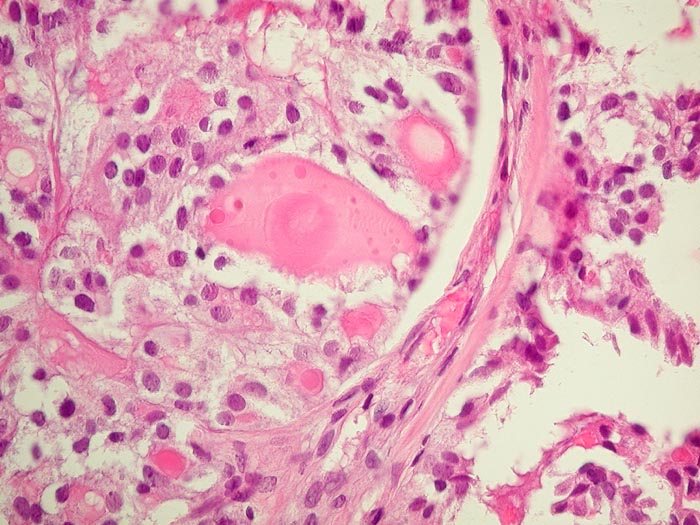

Metastase follikuläres Schilddrüsenkarzinom

Knochen, Becken

Die Metastase zeigt eine Morphologie vergleichbar mit normalem Schilddrüsenparenchym.

Die Tumorzellen reagieren positiv mit Thyreoglobulin sowie mit dem nukleären Transkriptionsfaktor TTF-1

Kein bekanntes Schilddrüsenkarzinom. Vor 30 Jahren Adenokarzinom des Kolons.